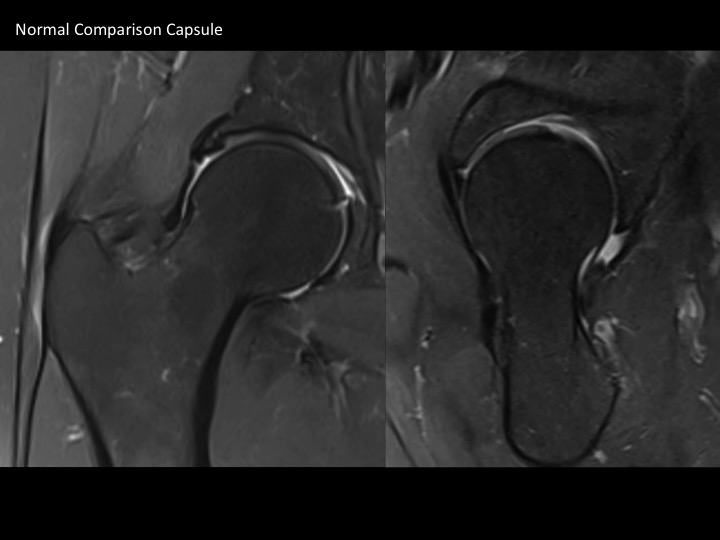

There is marked dark signal capsular thickening anteriorly and superiorly (white arrows). The reference, based on arthrography, refers to much thinner capsular measurements, and does not specify where measurements are made (these are mid superior and anterior). Is this chronic adhesive capsulitis? There is also insertional G Minimus tendinosis (yellow arrows) and degenerative tearing of the anterior labrum. The patient specified that pain is worst posteriorly. Last image from a different patient today with comparatively normal appearing capsule. Reference article.